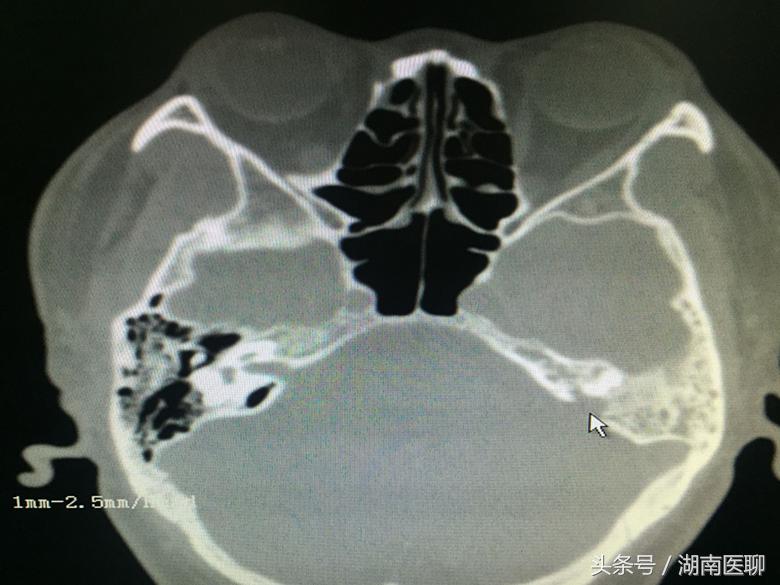

(影像资料上可以清楚地看到瘘口(鼠标所指位置))

通过核磁共振、CT检查发现,导致他多年来反复流清鼻涕、发热、脑膜炎的罪魁祸首竟然是脑膜穿孔。

脑脊液从穿孔处漏到耳内,然后经中耳与鼻腔通道进入鼻咽部,低头时以“清鼻涕”方式流出。